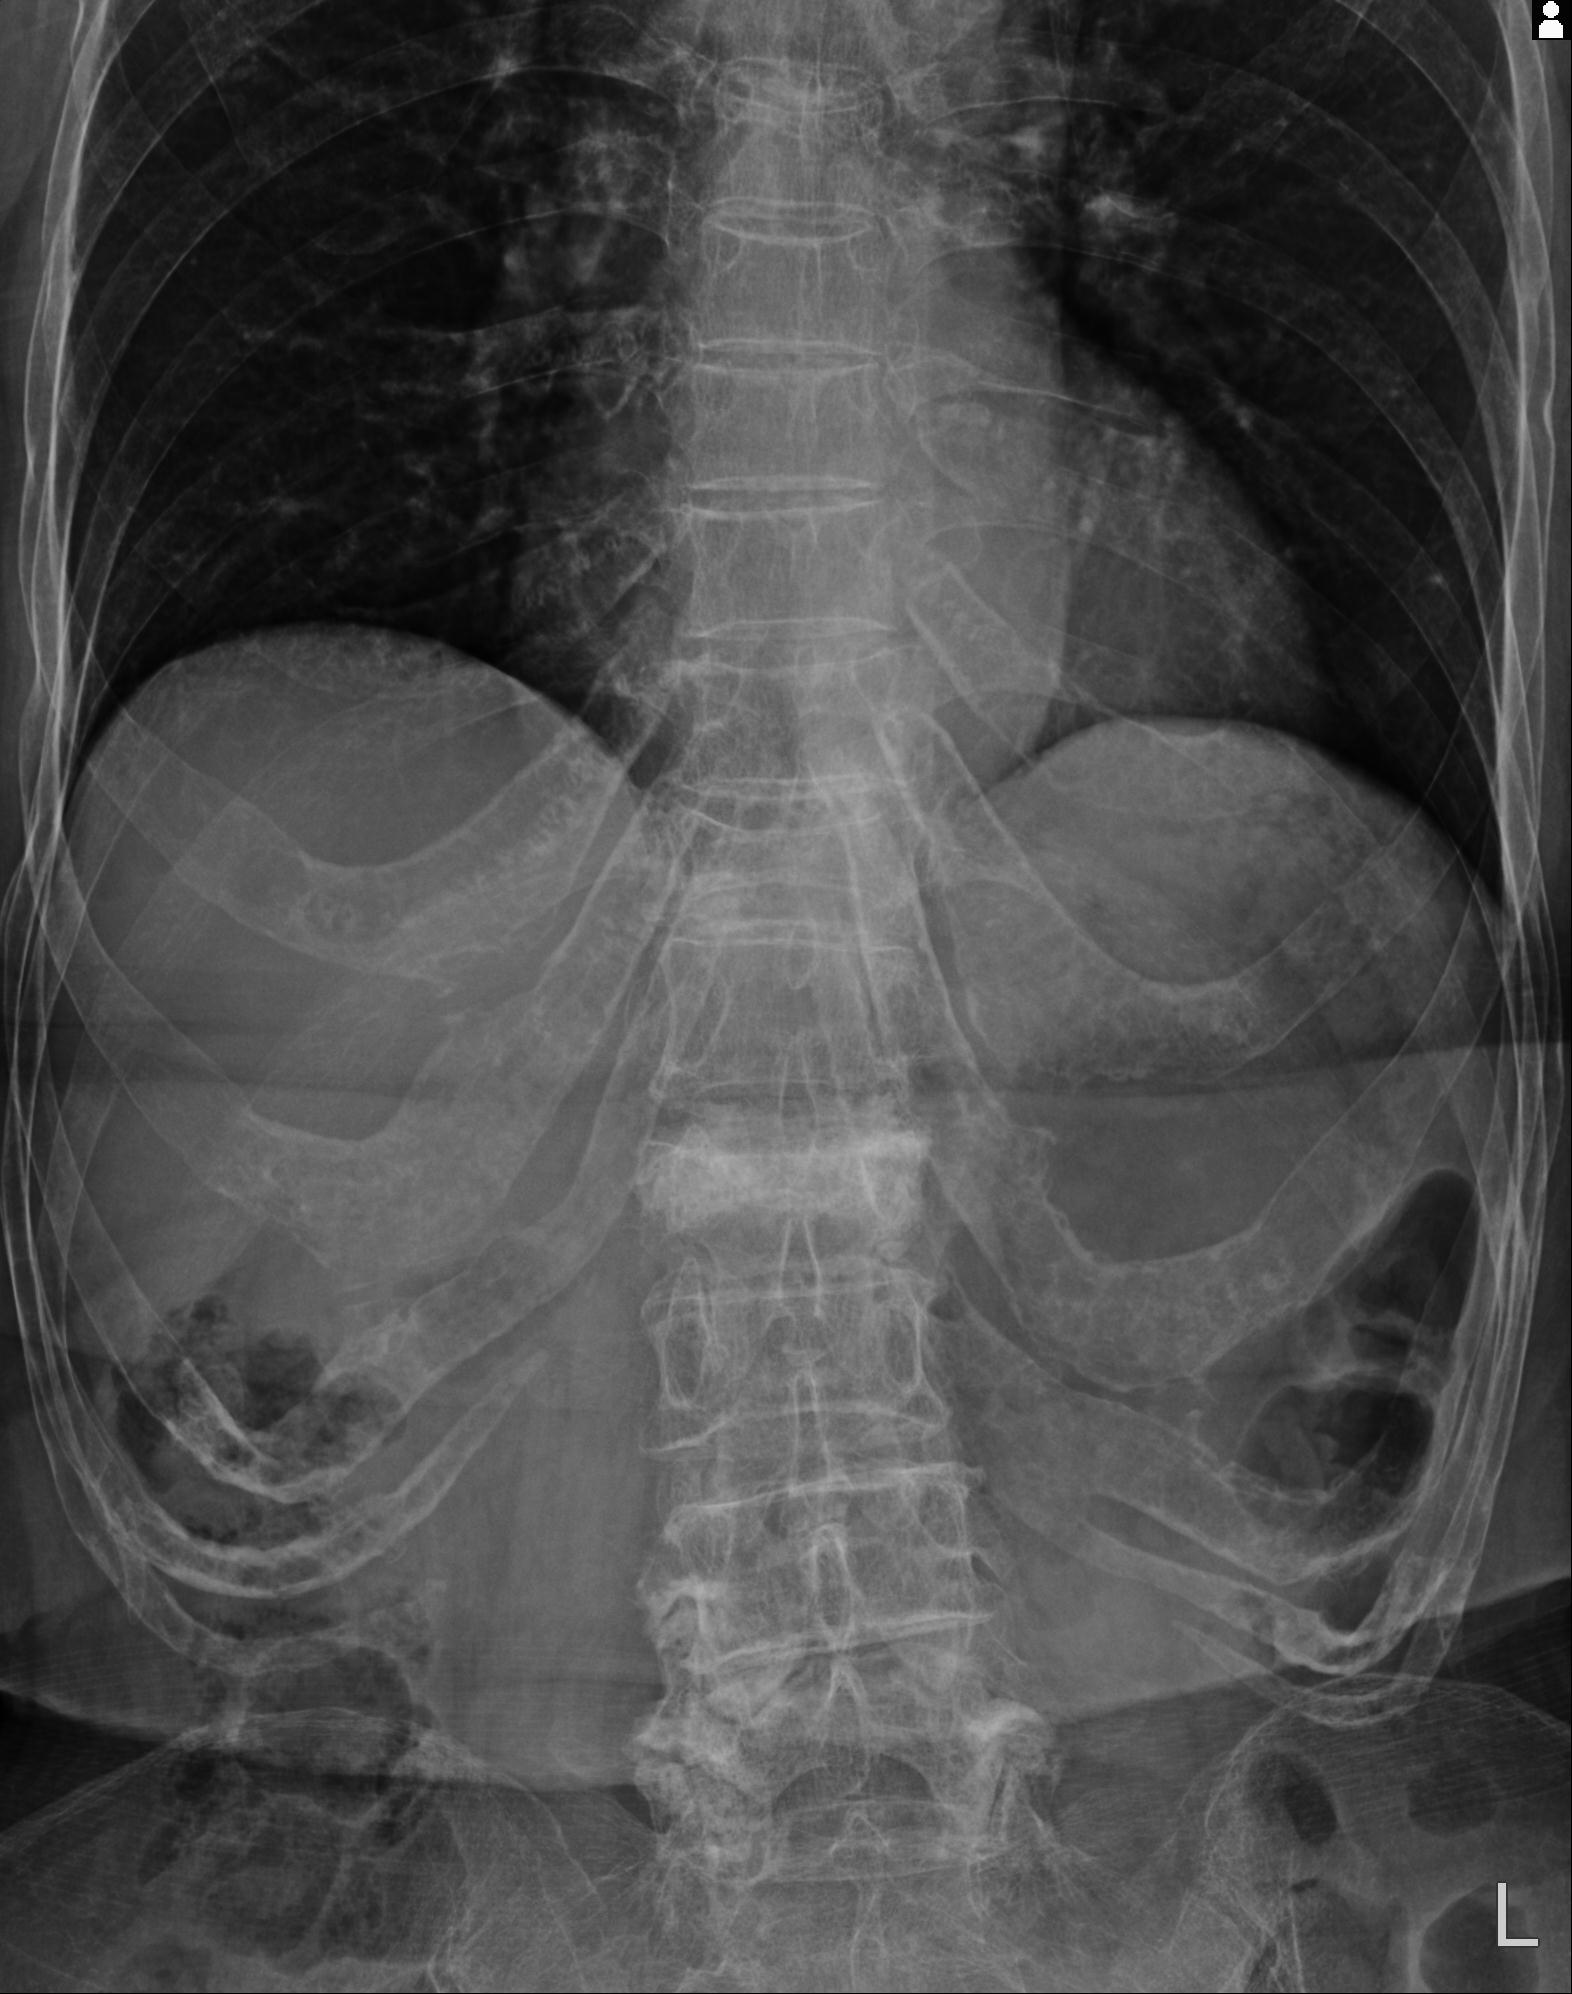

110286 2/17 股関節 2R 74歳女性 右人工骨頭

100703 1/27 両股正面+軸 1/29 両股正面+軸 94歳女性 パンソンロン

46666 1/28 両股正面+軸と 1/26 右手関節 2R 76歳女性 右転子部骨折

37 1/18 両股正面+軸 1/22 2R 86歳女性 右転子下

82084 1/14 1/20 股関節 2R 78歳男性 右人工骨頭

102811 1/13 股関節 2R 1/19 2R 80歳女性 右DHS

91569 3/25 両股正面とラウエン 70歳女性 人工骨頭+バンクーバー